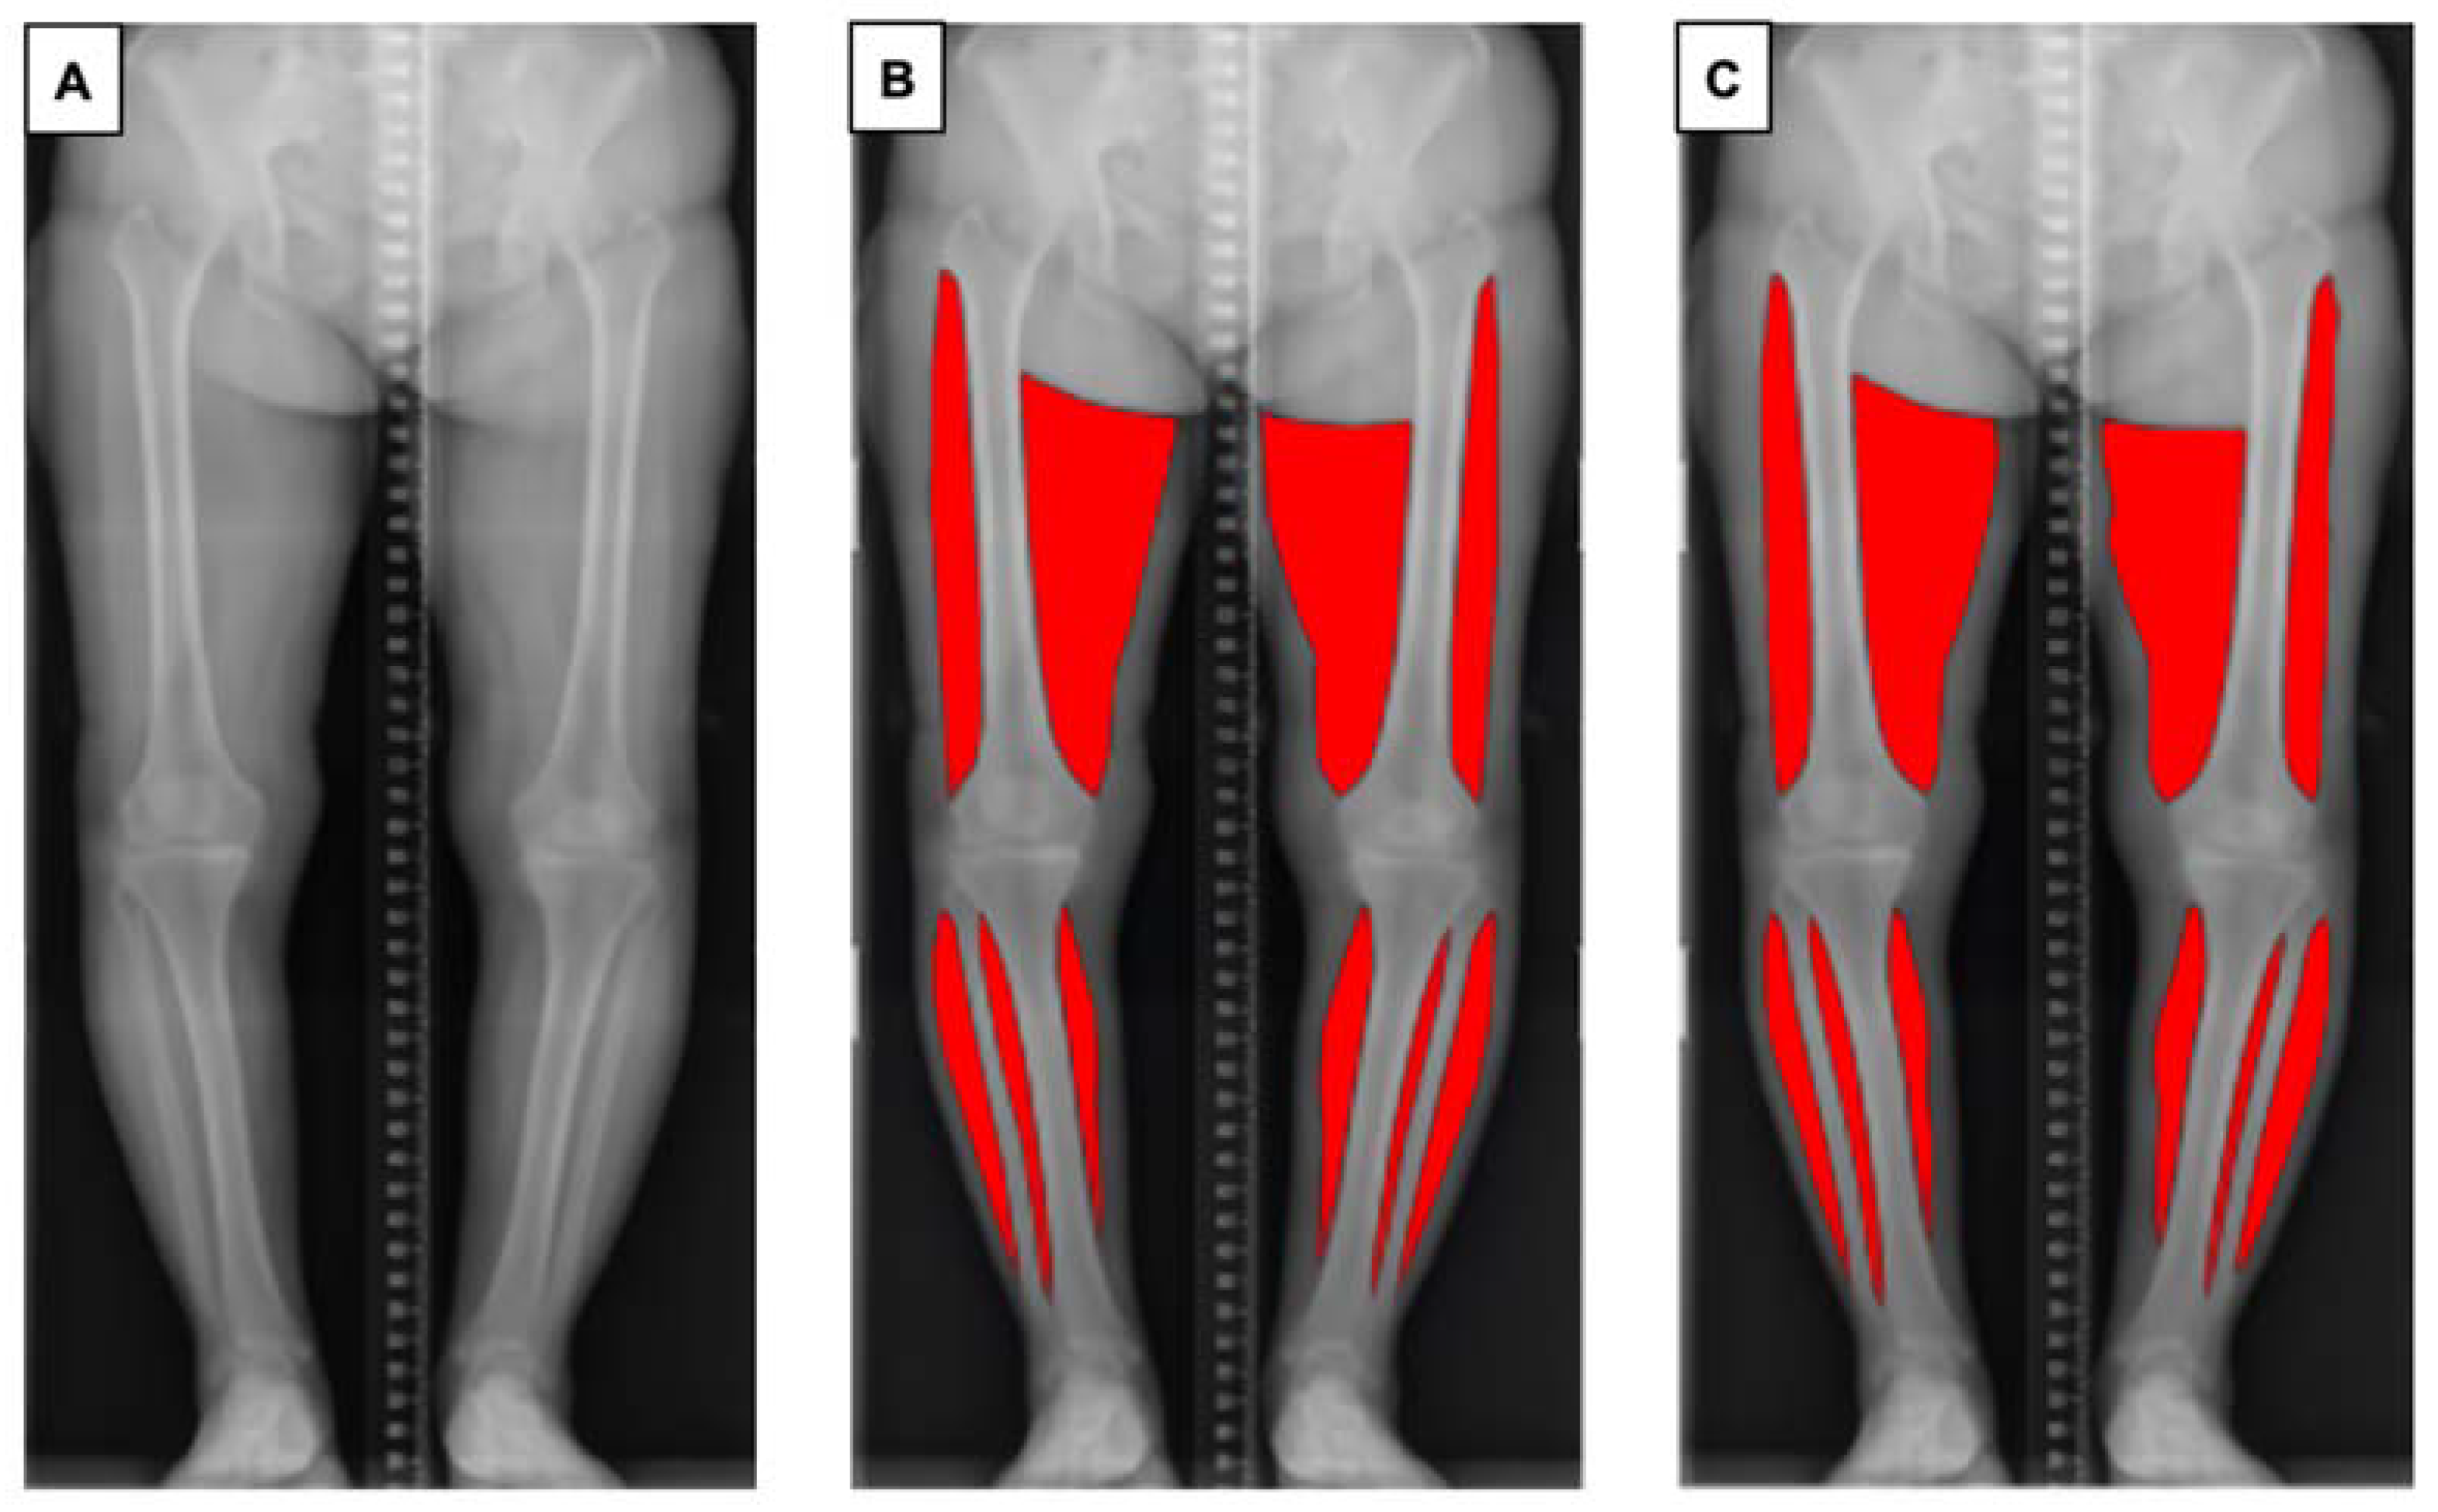

One of the authors (SA) trained in the segmentation task prepared 227 manually annotated images using Adobe Photoshop (Adobe, Mountain View, CA, USA) using a standardised protocol, to ensure consistency of the data. Muscles of the bilateral thighs and calves were annotated. The upper border of the thigh was determined as the greater trochanter of the femur (lateral) and gluteal fold (medial), and the lower border of the thigh was determined as the lateral epicondyle of the femur (lateral) and medical epicondyle of the femur (medial). The visible parts of the soleus and gastrocnemius muscle on coronal plane radiographs were annotated as the bilateral calf regions. Each ground truth segmentation was reviewed and revised by an orthopaedic surgeon with 14 years of experience (DR) (Figure 1).

Figure 1.

Overview of the pipeline for automatic muscle segmentation of full-leg plain radiographs. (A) Original radiographic image. (B) Ground truth mask of segmented muscle generated by the authors. (C) Segmented muscle predicted by the proposed model.